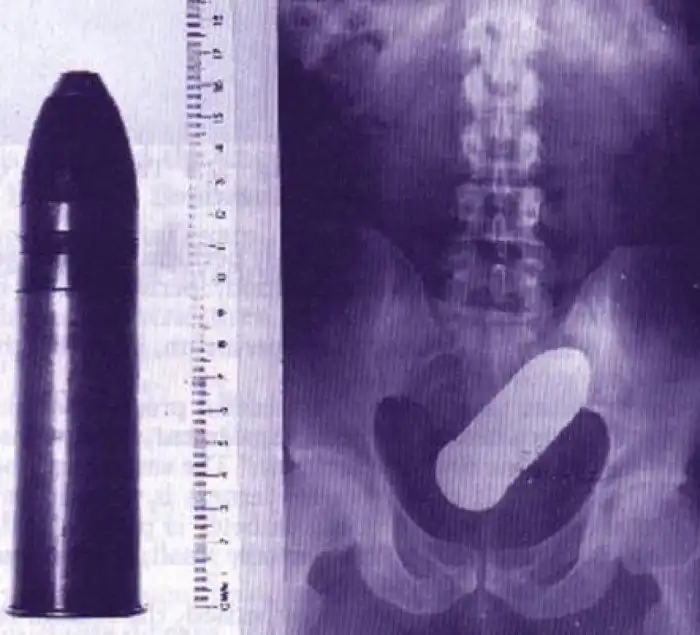

Хотя это и не так страшно, как артиллерийский снаряд.